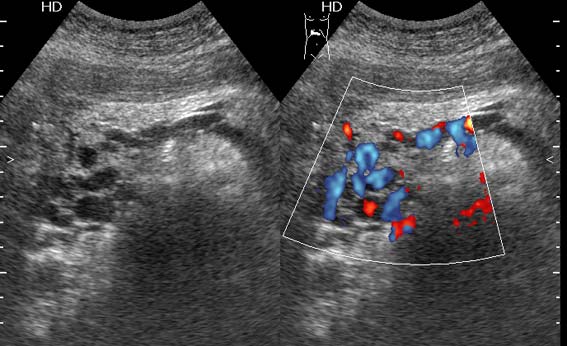

Тромбоз верхней брыжеечной вены

Женщина средних лет, клинический диагноз при поступлении - хронический панкреатит

Верхней брыжеечной

Да, действительно, формирование варикоза в области головки панкреас характерно для тромбоза верхней брыжеечной вены.Брехт писал(а):Верхней брыжеечной

Ургентность здесь относительная, это неострый тромбоз - для развития коллатералей необходимо время. В хирургической клинике при хроническом панкреатите мы нередко видим тромбозы воротной вены, селезеностой вены. Но тромбоз ВБВ встречается нечасто и заподозрить его можно по "гроздьям" варикозов в области головки панкреас. На пилетромбоз обычно указвают "гроздья" варикозов в воротах печени.besliu писал(а):Спасибо за случай,впервые вижу такую патологию,ургентность в поликлинике не так уж частая![]()